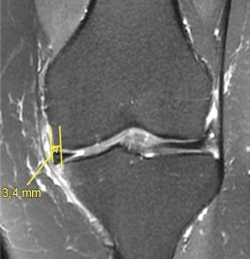

5. La bibliografía actual refiere varios factores predictivos de malos resultados o incluso de fracasos en el tratamiento mediante MPA: índice de masa corporal (IMC) elevado, lado externo, lesiones condrales, edema de médula ósea, extrusión meniscal (Figura 6) y meniscectomía total o subtotal (grado C).

Figura 6. Extrusión del menisco interno (> 3 mm) en un paciente con artrosis incipiente (resonancia magnética: proyección coronal; T2 SG).

4. La extrusión meniscal (Figura 6) se ha asociado con osteonecrosis local tras MPA (grado C).